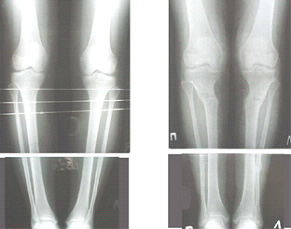

Вот ещё картинки, которые отправлял в Ортопод. Коррекция кривизны и удлинение на 3 см.